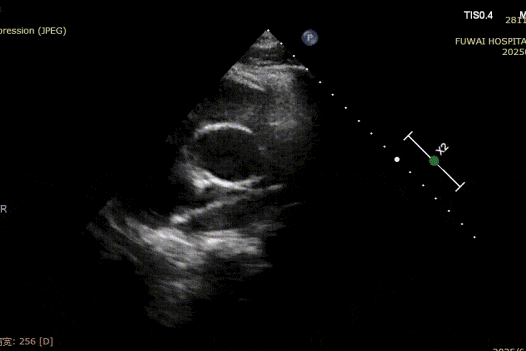

1-day postoperative TTE revealed that the occluder is in good shape without residual shunt (see last figure).